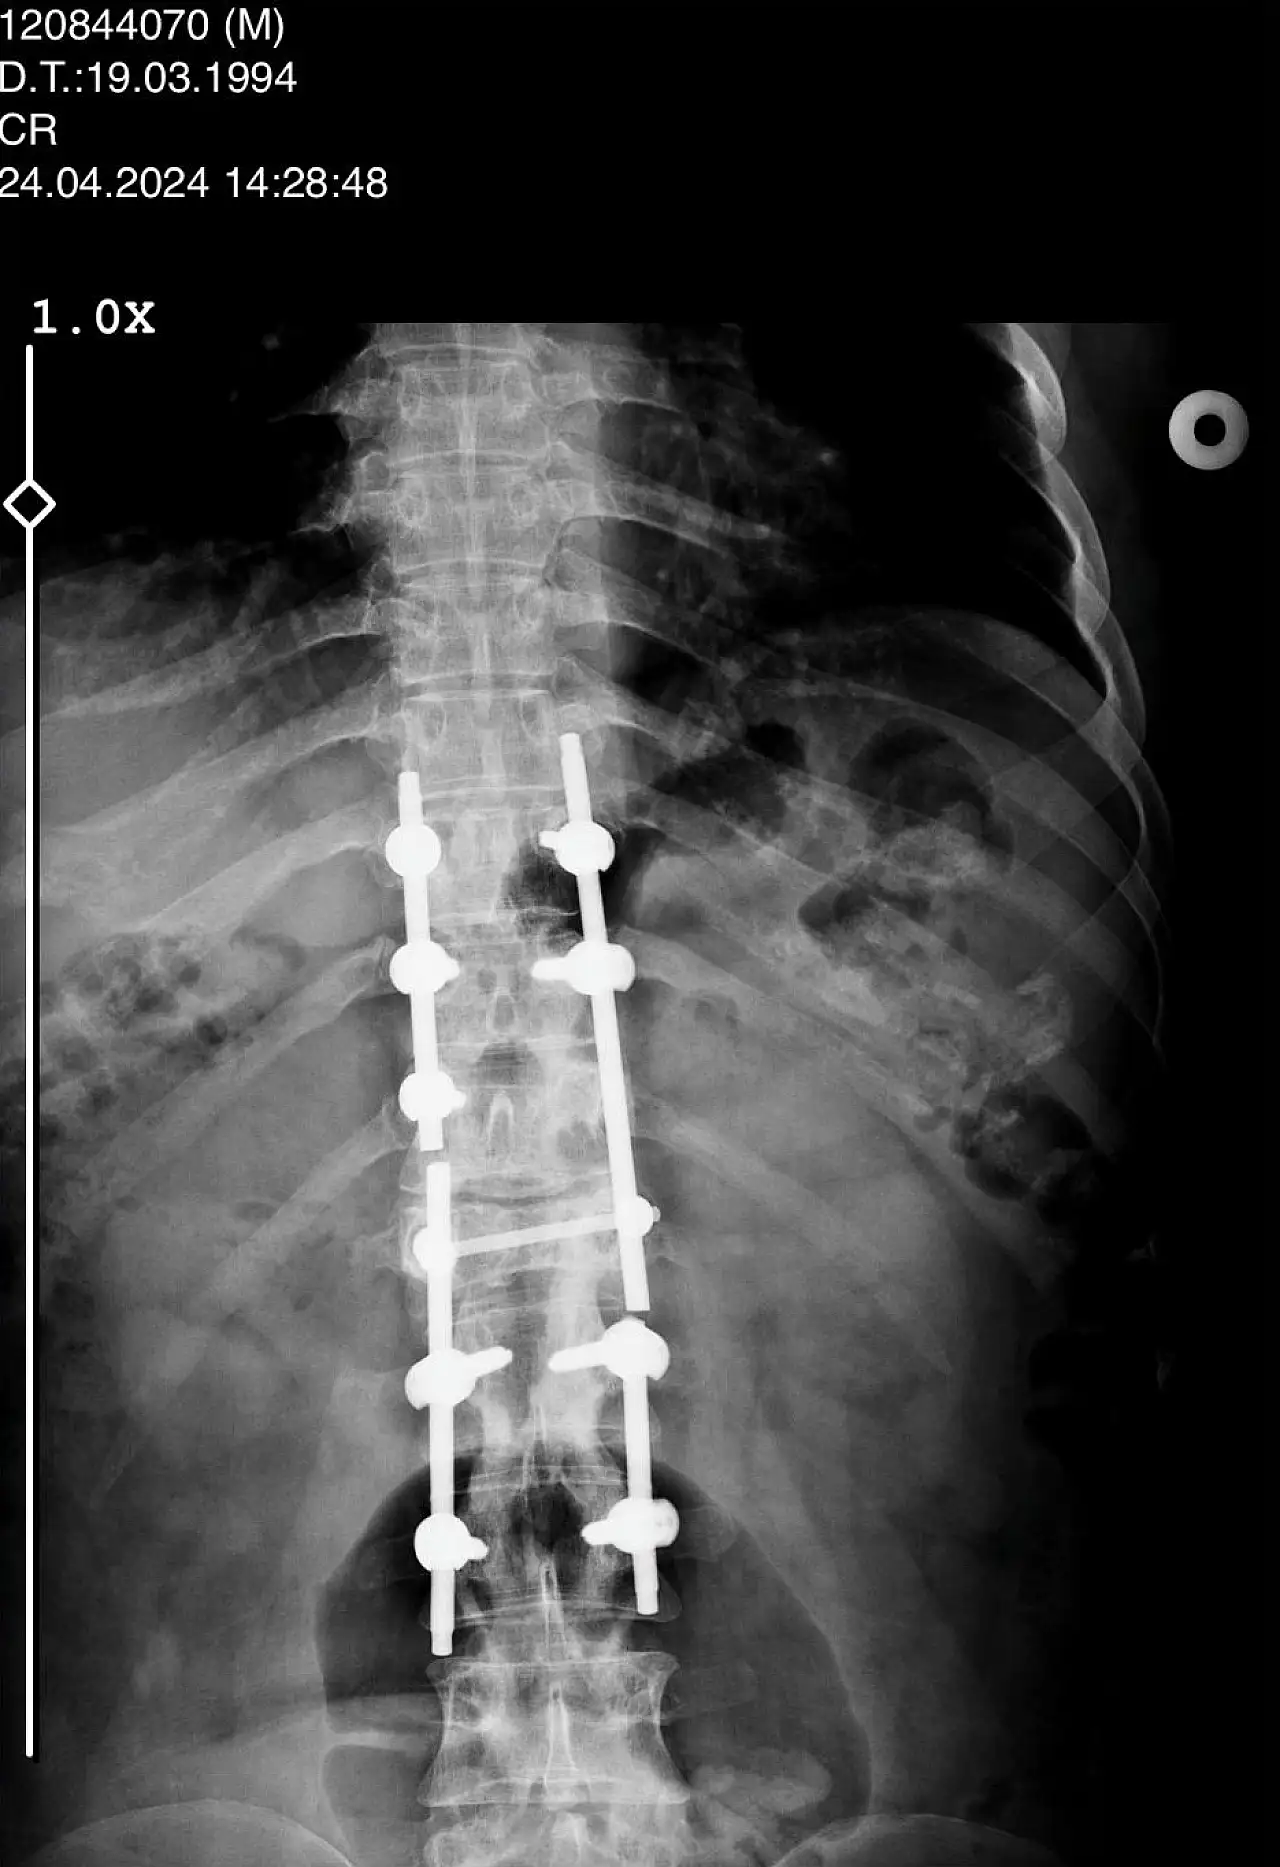

Konya'da bulunan Afşar ve Bağbaşı Barajı arasındaki Mavi Tünel'in inşaatında Palet İnşaat bünyesinde ekskavatör operatörü olarak çalışan 31 yaşındaki Sezgin Keşto, 1 Mart 2019 tarihinde 54 yaşındaki Cezmi Çelik'in idaresindeki beton mikserinin kaza yapması neticesinde ağır şekilde yaralandı. O esnada sürücü Cezmi Çelik ise hayatını kaybetti. Araçtan çıkarılmasının ardından Selçuk Üniversitesi Tıp Fakültesi Hastanesi'ne kaldırılan Keşto'nın omurgasının kırıldığı, omuriliğinin zedelendiği tespit edildi. Geçirdiği ameliyat sonrası 3 gün yoğun bakımda kalan Keşto, 6 aylık tedaviden sonra taburcu edildi. Bir daha yürüyemeyeceğini öğrenen Keşto, Adana'da ikamet eden ailesinin evine döndü.